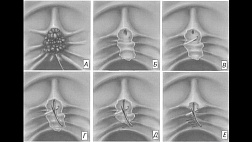

Может быть рак. Желчный пузырь удаляют. Очень повезет, если хирург возьмется удалять такой желчный пузырь лапароскопически.